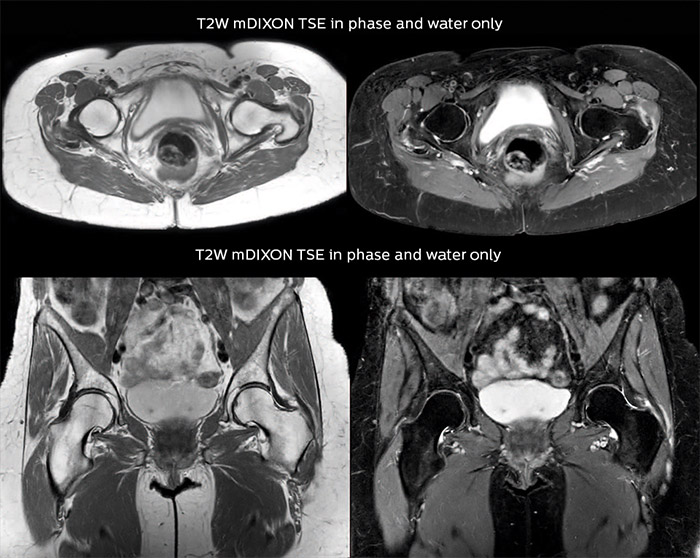

“For bone assessment near joints, mDIXON TSE provides the visualization and multiple contrasts to describe abnormalities within a limited number of acquisitions. Bone marrow signal abnormalities are common MRI findings that can represent various underlying causes, from normal variance to malignancy. So, it is important for us to notice and characterize these findings. With different contrasts, both with and without fat signal as mDIXON TSE efficiently provides, we can make a confident diagnosis.” “Other examples in bone are the signal description of a necrotic fragment in osteonecrosis, the signal description of tumoral matrix that has different components (necrosis, hemorrhage, cartilage, bone formation). These are all possible thanks to in-phase and water images from a single mDIXON acquisition.”

Fat suppressed images appear homogeneous over the entire image, even with large coverage at 3.0T – for instance in scapular or hip girdles – or in the bearing areas or around metal prostheses, where fat suppression is often deficient with STIR or spectral fat suppression, causing diagnostic difficulties. If a diagnostic image is right the first time, we don’t need to repeat or add a sequence.” “mDIXON TSE sequences allow simultaneous characterization of morphological changes from the in-phase T2-weighted images and visualization of edematous changes, thanks to the water T2-weighted images from the same acquisition. Anatomical and morphological considerations could be a partial or complete ligament tear, a bony avulsion or hematoma.” “For soft tissue assessment mDIXON brings similar benefits. For example in one T2-weighted mDIXON TSE acquisition, having the multiple contrasts helps us assess abnormalities in peripheral nerves fascicles, which may be due to anatomical or inflammatory changes..”

“In our spine cases, we use mDIXON TSE for patients with degenerative and inflammatory spine issues, vertebral fractures and vertebral and paravertebral tumor characterization,” says Dr. Lefebvre. “It provides, in a single acquisition, different contrasts so we can both visualize and characterize spinal, focal or diffuse spine lesions.”

“mDIXON TSE makes real a difference in cases of acute and traumatic spinal injuries, where it allows us to reduce the scan time by only using a limited number of sequences. For patients in pain, who come from the emergency unit and need surgery, for example, MRI must be very fast. With a single T2-weighted acquisition we can assess spinal cord, vertebral disc and ligament wholeness with in-phase images, as well as trabecular fracture and edematous changes with water images.” Dr. Lefebvre cites other frequent examples of spinal diseases that benefit from the mDIXON technique. “In cases of vertebral disc herniation or degenerative discs, for example, we don’t have to choose between fat or no fat images. We can assess morphological changes in the endplate with in-phase images from T2-weighted sequences and in the water image from the same acquisition we will see inflammatory changes into endplates.”